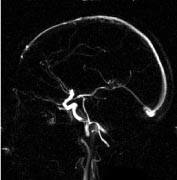

Bildeopptaket kan gjøres med to- eller tredimensjonal teknikk (henholdsvis 2D- eller 3D-innstrømnings-MRA). Ved 2D-teknikken registreres de induserte strømsignalene fra en tynn skive om gangen, og i løpet av et bildeopptak dekkes den aktuelle anatomien av mange skiver kant i kant eller med en viss overlapping. Denne teknikken er sensitiv for langsom (venøs) blodstrøm fordi det i hvert snitt bare er en kort blodsøyle som behøver å erstattes av friskt blod utenfra (fig 2). Ved 3D-teknikken registreres signalene fra et større, avgrenset volum, og teknikken er derfor avhengig av høyere (arteriell) blodstrømshastighet for å fornye blodet i de dype deler av volumet. 3D-innstrømnings-MRA gir best romoppløsning og er mer egnet enn 2D-teknikken til å vise slyngede kar (fig 3).

Intrakraniale kar

Kontrastforsterket MRA har foreløpig for dårlig romoppløsning for intrakranialt bruk. Den MRA-metoden som er best egnet for fremstilling av intrakraniale arterier, er 3D-innstrømnings-MRA (fig 3). Ved hjelp av denne metoden kan man påvise stenoser og okklusjoner av de større arteriene. Både MRA og CT-angiografi kan fremstille intrakraniale aneurismer med diameter på 5 mm eller mer med stor nøyaktighet (10, 11), for mindre aneurismer synes CT-angiografi å være noe bedre enn MRA. De ikke-invasive metodene kan bidra ved planlegging av behandling av aneurismer (kirurgisk eller radiologisk intervensjon), men metodene har ennå ikke kunnet erstatte kateterangiografi (12). Ved intrakraniale arteriovenøse malformasjoner er MR-snittbilder den metoden som best viser den anatomiske lokaliseringen av nidus (13). MRA kan gi en bedre anatomisk oversikt over hele malformasjonen, særlig om man benytter fasekontrast-MRA, som gir best fremstilling av både arterie- og venesiden. Både kirurgi og endovaskulær embolisering krever imidlertid en detaljfremstilling som bare kan gis av kateterangiografi.